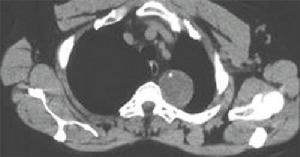

1、X 線胸片 少量積液可僅表現為患側肋膈角模糊、變鈍或消失;中等量積液可見患側下胸部大片均勻的緻密陰影,上緣呈外高內低的弧形;大量積液時患側胸部呈大片均勻的緻密陰影,氣管和縱隔對側移位,患側膈肌下移;包裹性積液表現為大小不等的圓形或半圓形均勻的緻密陰影,邊緣光滑清晰;葉間積液在側位片上呈長軸與葉間裂一致的邊緣銳利的梭狀均勻的緻密陰影;肺底積液在正位片上易與膈肌升高混淆,患側臥位透視或拍片則可見膈肌水平正常,胸水沿下側胸壁分布。X 線檢查不僅可以診斷積液,而且有助於原發病的診斷。

2、CT 和MRI 檢查 CT 和MRI 具有對密度分辨力高和二維圖像的特點,可以很好地區分液體與實體影,能很好地顯示X 線平片盲區的小病灶或少量積液,能突現出被胸水掩蓋的肺內塊影,還有助於區分積液的性質。